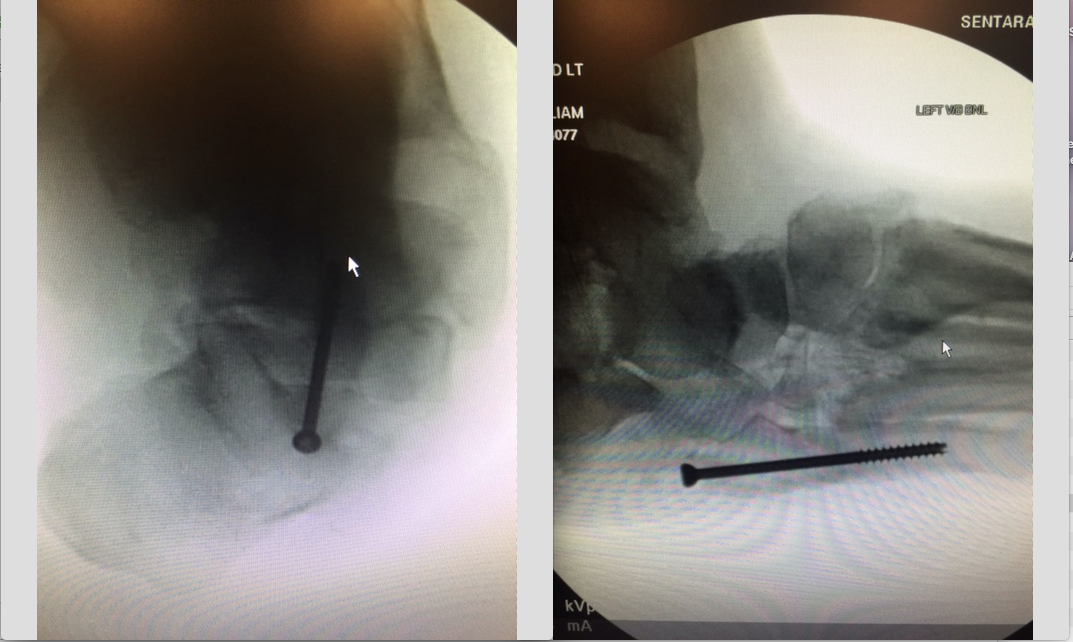

The limited soft tissue dissection and load sharing capabilities of beam screws are tailored for the biologic and biomechanical demands of the patient with Charcot.1 Grant and colleagues reviewed radiographic changes and outcomes for patients who had Charcot foot reconstruction over a 14-year period. In this study, surgeons performed beaming on 71 Charcot foot deformities in 70 patients. Twenty-two of the deformities were an isolated hindfoot deformity, 20 were an isolated Lisfranc deformity and 29 were a combination of hindfoot and Lisfranc deformities.

Reconstructive surgery for one group in the study involved only medial and lateral column beams.1 For another group in the study, surgery involved reconstruction with medial and lateral column beams in combination with either a subtalar arthroereisis or subtalar joint fusion. Both groups showed significant improvements in radiographic alignment, including Meary’s angle, the tarsometatarsal angle, the talonavicular angle and the calcaneocuboid angle. The study authors noted that the group that only had medial and lateral column beams also demonstrated a significant improvement in the calcaneal inclination angle whereas the second group did not. In both groups, authors note the surgical intervention maintained the correction and was useful for Charcot reconstruction.

Unpublished research from our institution also suggests that placing a screw across the subtalar joint produces better long-term survivability. This makes sense to our team from the perspective of bending moments across the arch of the foot. The more beams one adds to a static medial column system, the more beams share the load. Therefore, placing a beam through the second metatarsal, into the lesser tarsus and into the talar neck shares the load of the medial column of the foot.